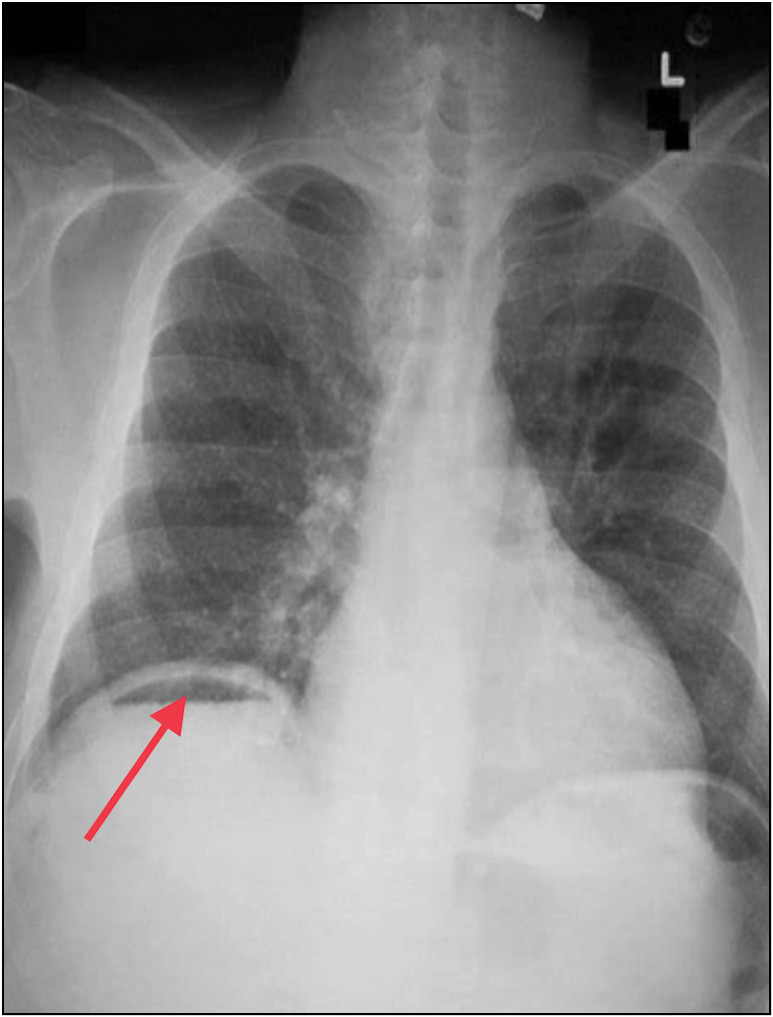

一名 53 岁的妇女因高烧伴寒战 15 天、右上腹疼痛 10 天前来外科急诊就诊。腹部 X 光片和胸部 X 光片显示右半膈下有游离气体。由于没有全身或局部腹膜炎的迹象,急诊开腹手术被推迟。随后,腹部造影剂增强计算机断层扫描显示该患者患有气肿性肝脓肿,在超声波引导下对脓腔进行了引流。

A 53-year-old woman presented to the surgical emergency with complaints of high-grade fever accompanied by chills for 15 days and pain in the right upper abdomen for 10 days. X-ray of the abdomen and chest X-ray revealed free gas under the right hemidiaphragm. As there were no signs of generalised or localised peritonitis, emergency laparotomy was postponed. Subsequently, a contrast-enhanced computerised tomography scan of the abdomen suggested an emphysematous liver abscess, which was managed by ultrasonography-guided drainage of the abscess cavity.